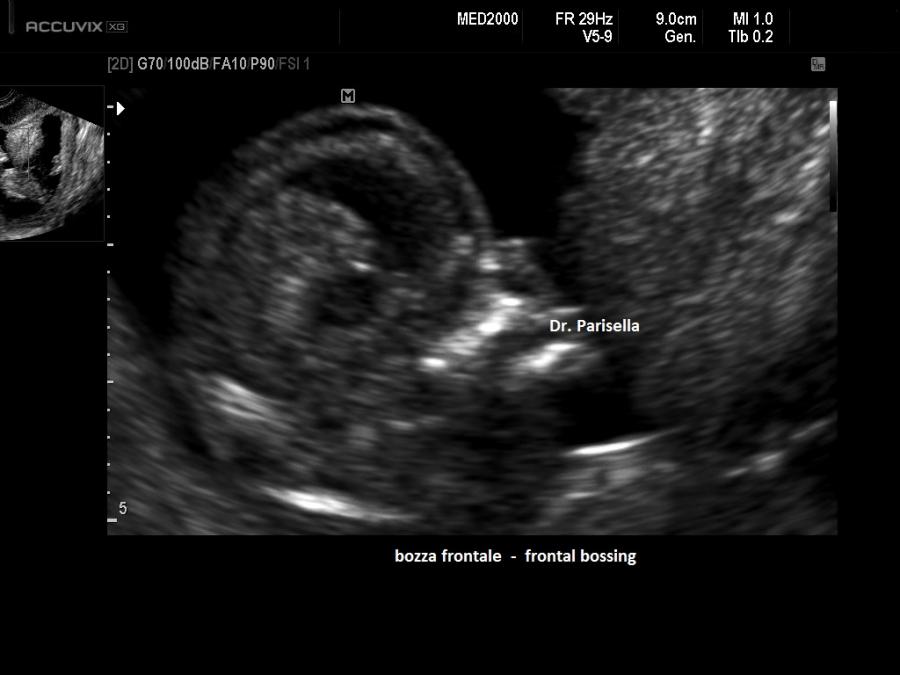

E' una malattia genetica rara caratterizzata da lussazione congenita poliarticolare tra cui il Congenital Genu Recurvatum (bilaterale), piede torto, mano torta e caratteristica facies caratterizzata da ipertelorismo, radice del naso depressa, bozza frontale prominente, micrognazia e palatoschisi.